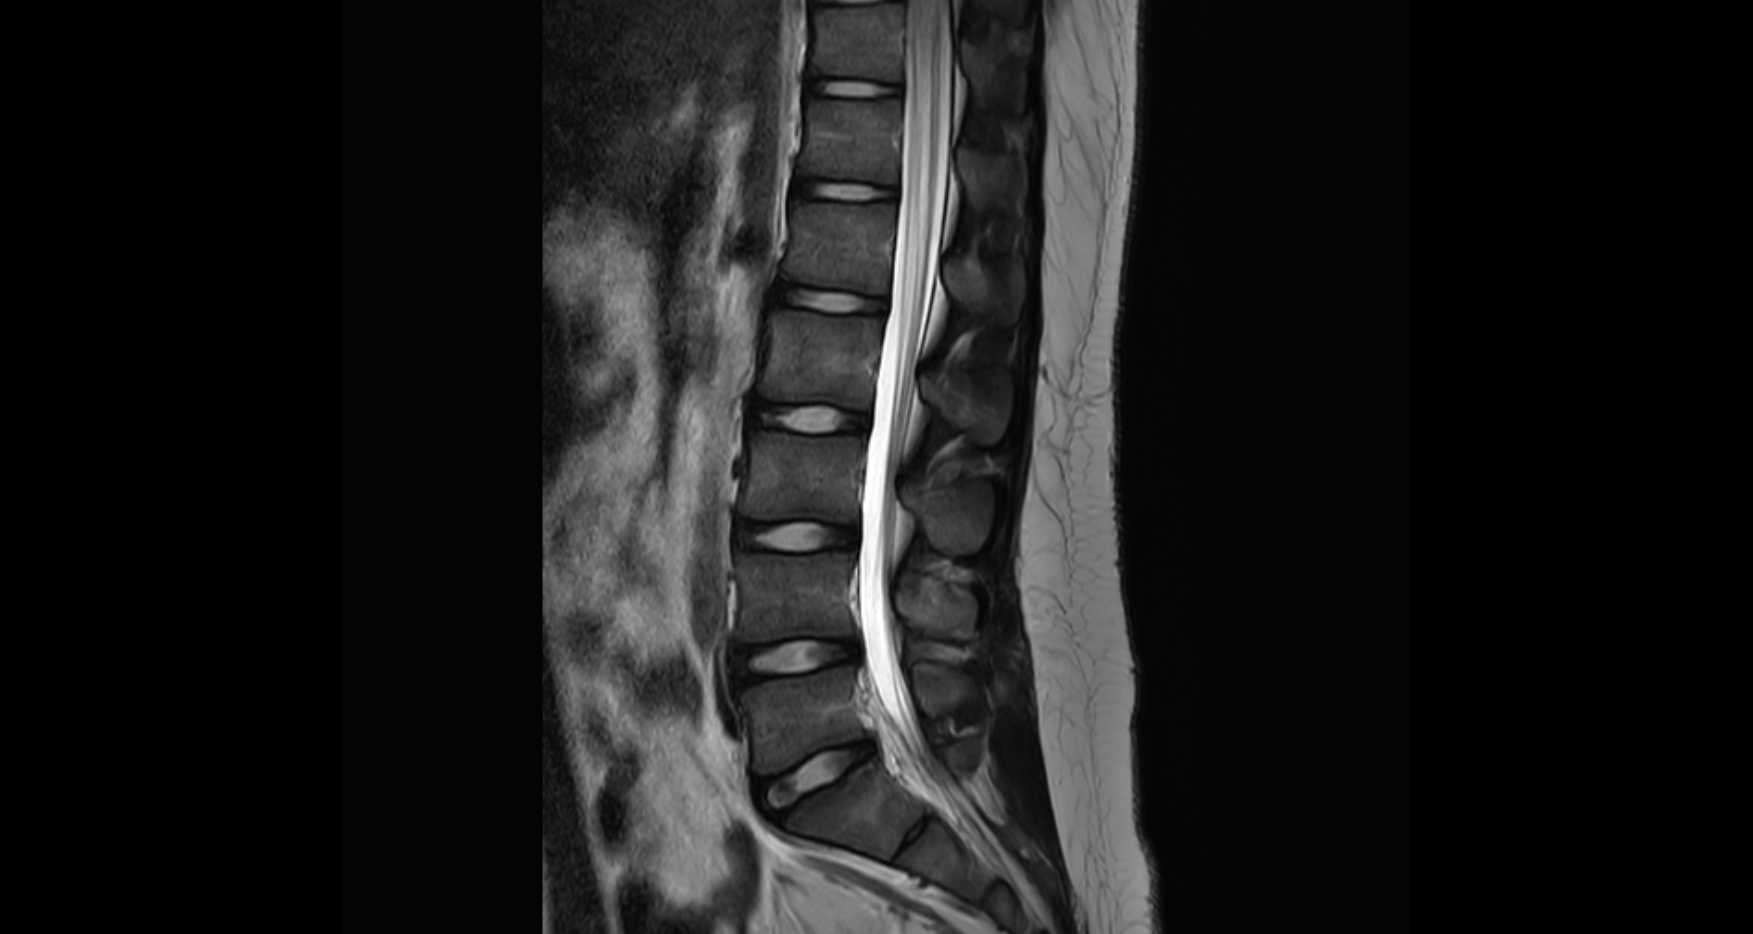

Lumbar Disc Nomenclature [ 24.06.30]